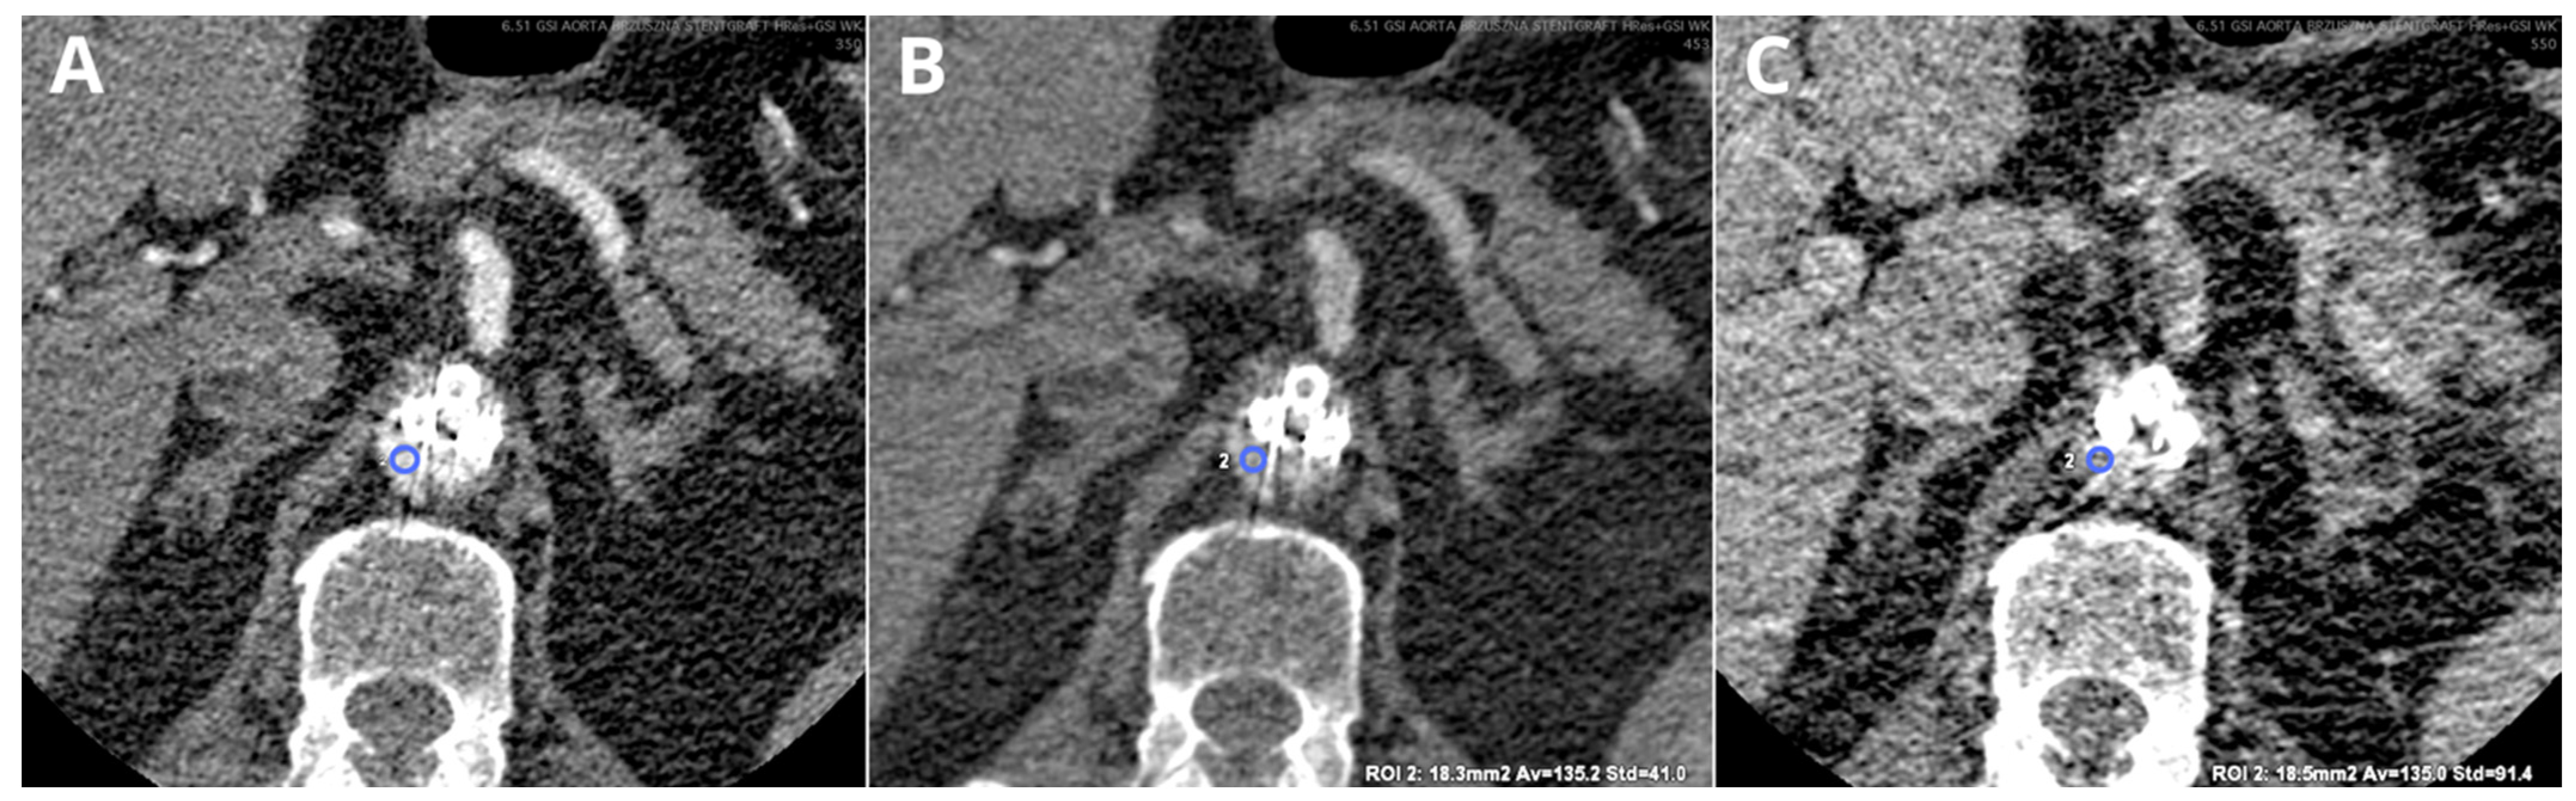

- Kazimierczak, W.; Nowak, E.; Kazimierczak, N.; Jankowski, T.; Jankowska, A.; Serafin, Z. The Value of Metal Artifact Reduction and Iterative Algorithms in Dual Energy CT Angiography in Patients after Complex Endovascular Aortic Aneurysm Repair. Heliyon 2023, 9, e20700. [Google Scholar] [CrossRef]